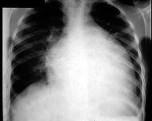

问题 男,24岁,反复胸闷气短4年,近1周加重,端坐时即感胸闷,伴咳嗽、下肢水肿,肝脏肿大。超声心动图示心脏扩大,室壁变薄,EF值20%,二尖瓣、三尖瓣中度反流。胸片如图所示。 可能的诊断是 ( )

选项 A、心肌炎 B、扩张型心肌病 C、先天性心脏病 D、肺心病 E、风湿性心脏病二尖瓣关闭不全

答案 B